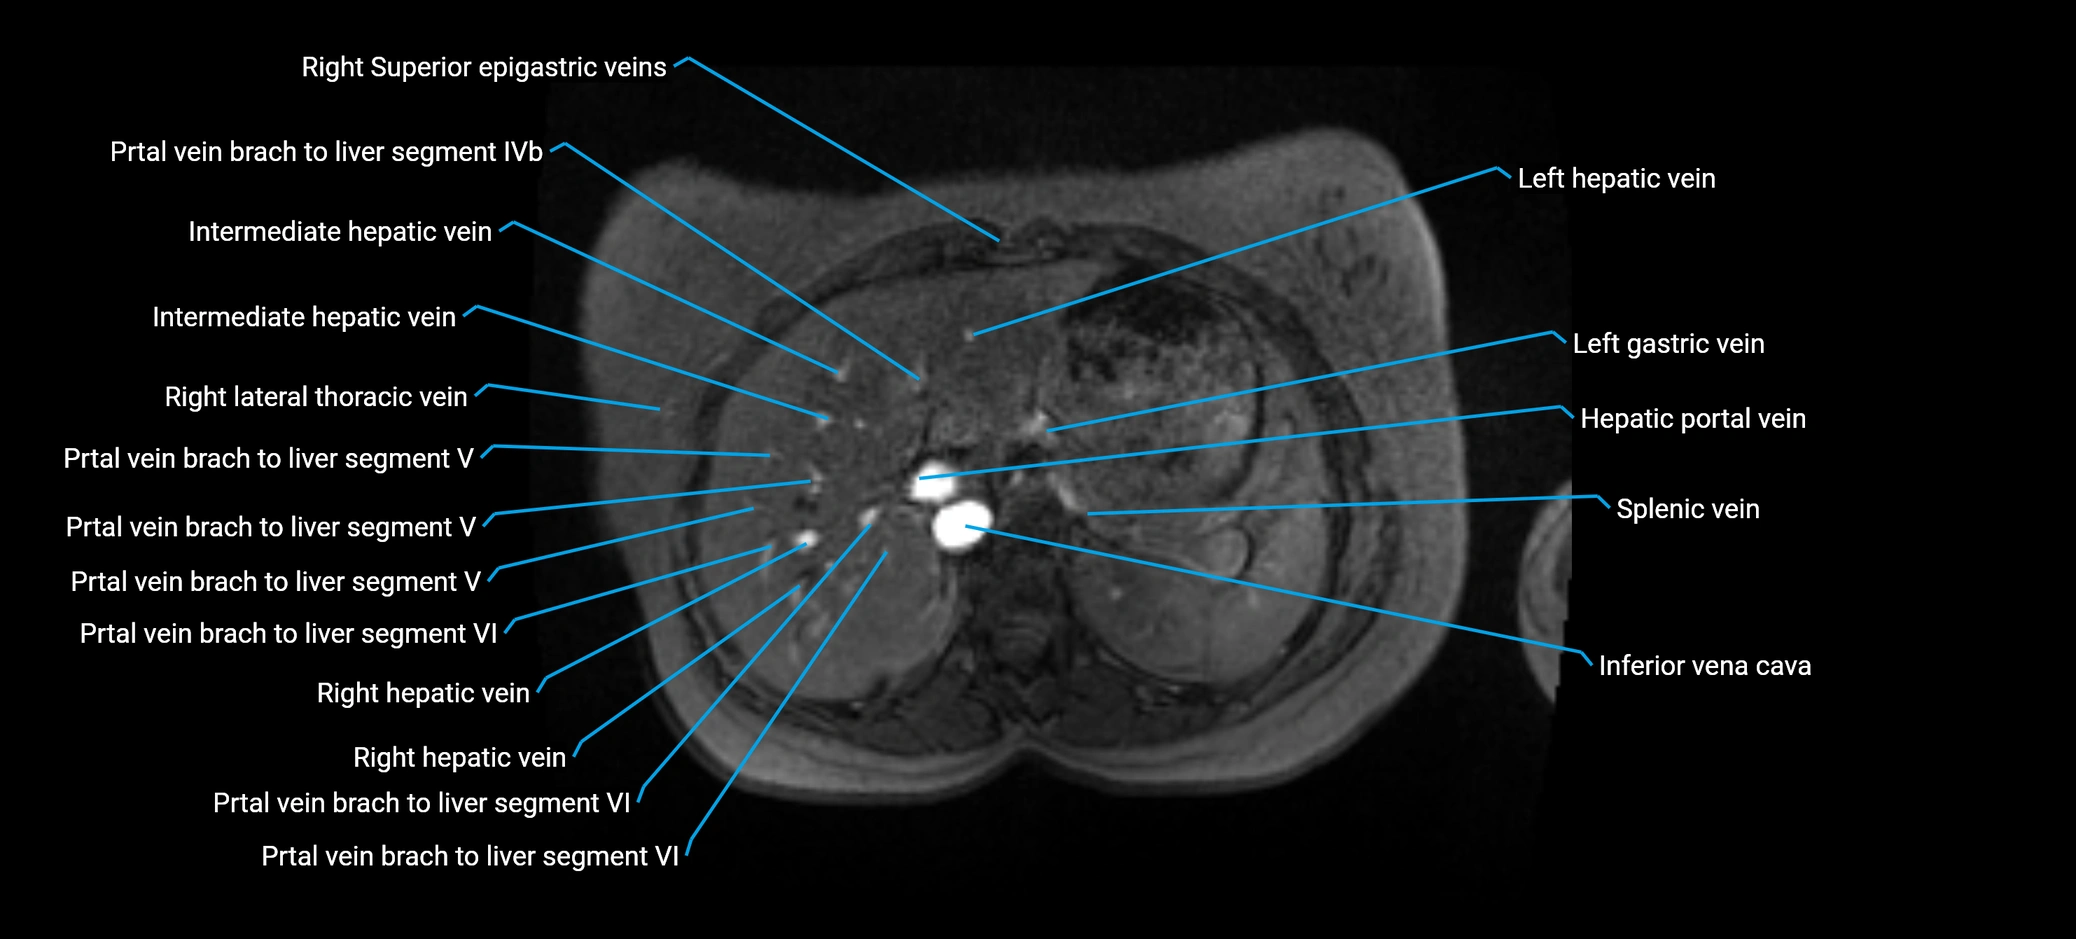

MRI image

image